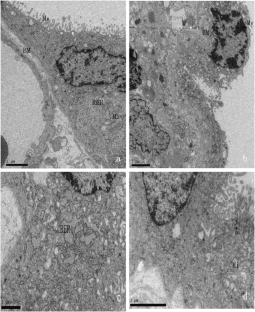

Fig. 1